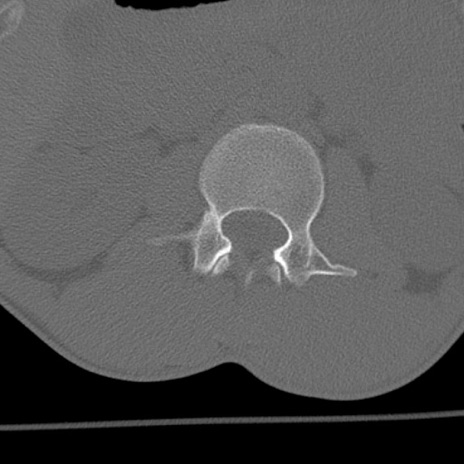

症例3 腰椎CT(横断像)

腰椎CT